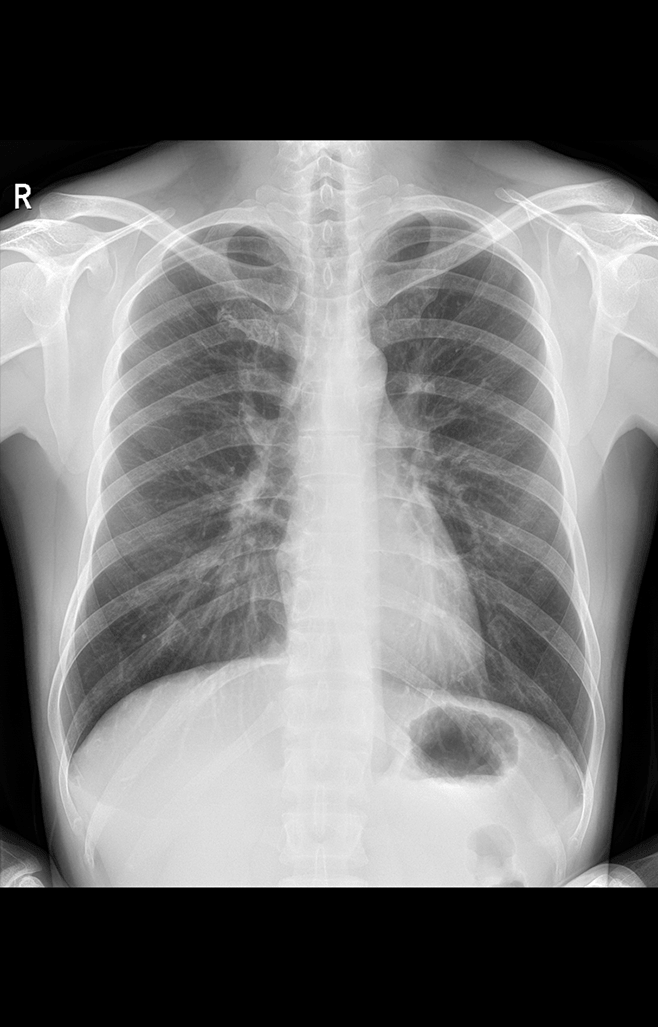

高清動態平板探測器

搭載自主研發超清大視野動態平板探測器,600微米碘化銫大幅提升X線轉化效率,獨特的非晶硅陣列與高速讀取集成電路緊密協作,輕松實現多幀率透視與高清點片。

17x17英寸

大幅面成像 -

900萬

高清像素點片 -

線性探測平面

圖像無畸變、無失真

專業的影像處理系統

“騰靈”系列搭載的IEAE影像處理系統,具備多項發明專利。本系統采用多頻域圖像處理技術,其6大核心處理模塊使影像具有優秀的一致性、柔和性、空間層次感和紋理細膩度,為用戶精準診斷病灶奠定了堅實的基礎。